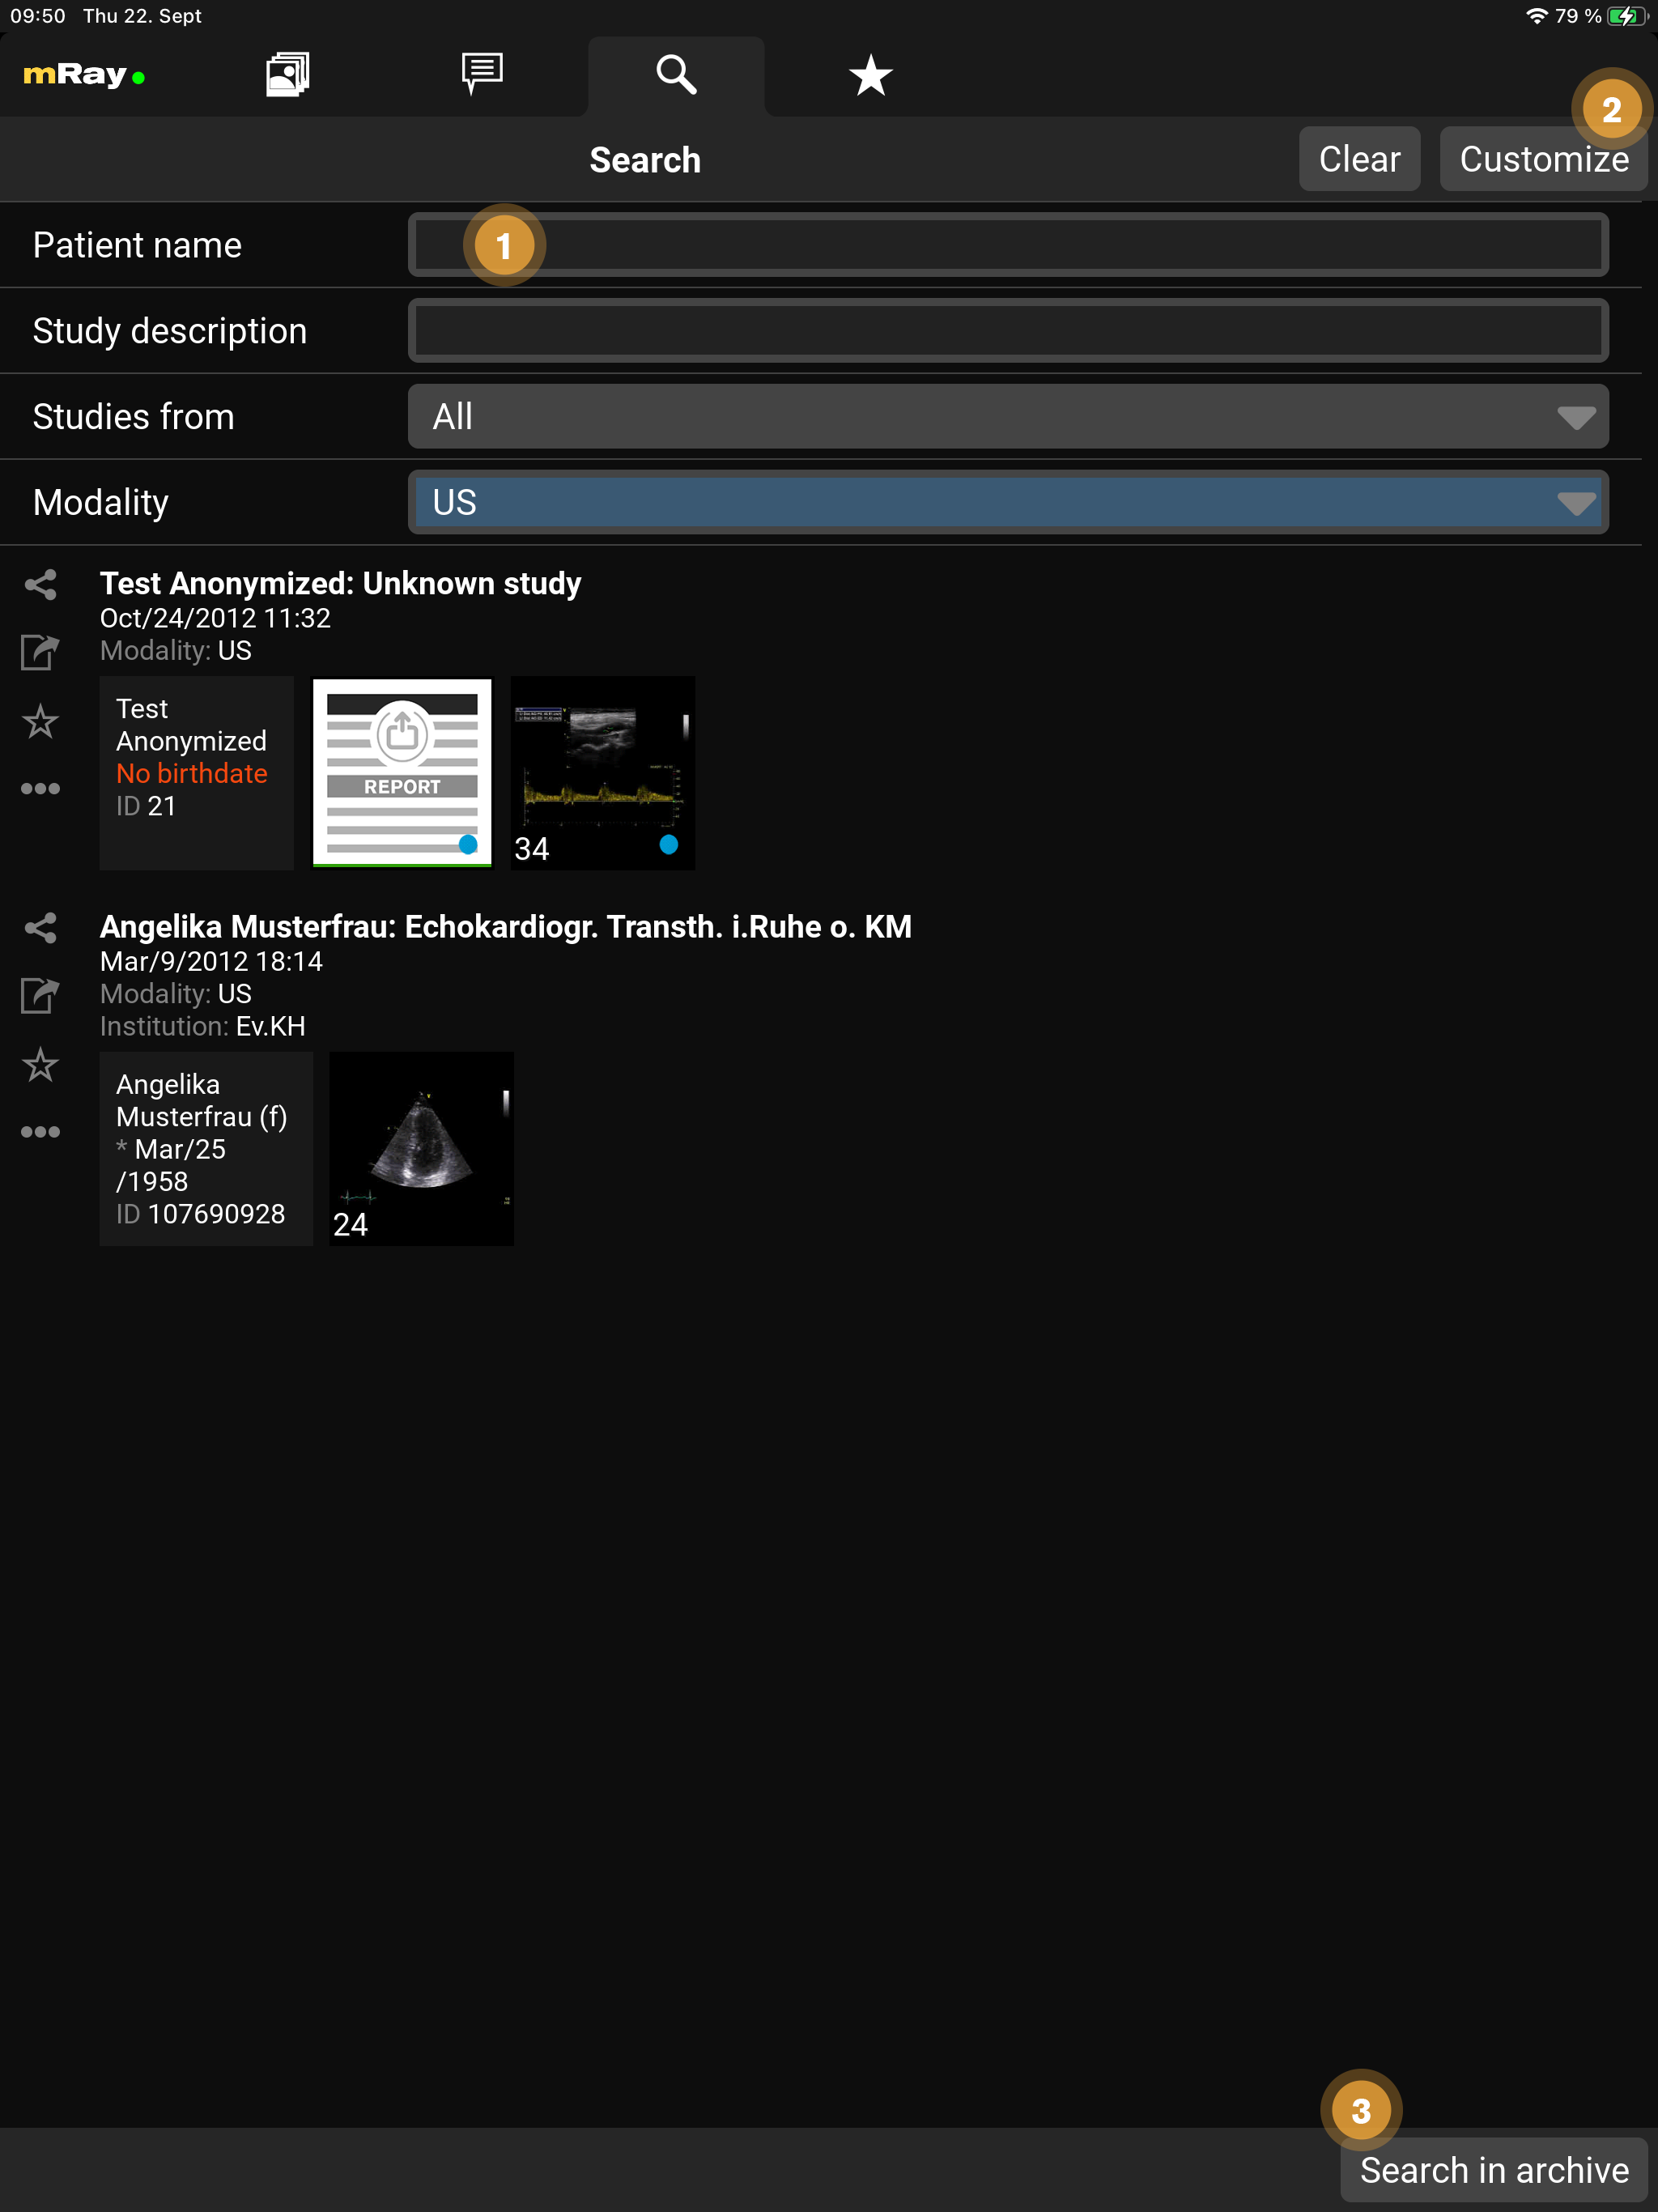

9.11. Search

With the search function you can search the database of your mRay server quickly and easily. The results list shows studies matching your search criteria. The search results can be moved to the inbox using the 'Offline available' button. You can also view records directly in the search or simply share them with a colleague. Note that, of course, only those records appear that you have been granted access rights to. If the desired data record does not appear in the list, it is possible to make a corresponding request via one or more connected PACS. The search fields can also be customized to suit your needs.

-

You can specify your search criteria here

-

The search fields can be customized by pressing this button

-

Send the search query to a PACS (available if your mRay server is configured accordingly)

The search fields can be customized and the following fields are available for selection:

-

Patient ID

-

Patient name

-

Birthdate

-

Study description

-

Studies from (date and period of study)

-

Modality

-

Referring Physician

-

Station (DICOM Tag Requesting Service)

-

Accession number

|

Note on the PACS Search

|

|

Please note the following general information on the PACS search

|